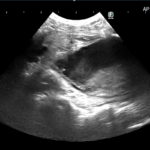

腹部超音波検査では前立腺実質エコーは均質であり、形状は通常左右対称である。前立腺炎の場合、実質は不均一であり、多巣性の低エコー領域が存在する。前立腺膿瘍および前立腺内嚢胞は局所的な単一または複数の無から低エコーの構造として現れる。